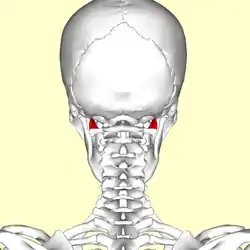

Posterior view of neck bones (rectus capitis lateralis muscle shown in red) | |

The rectus capitis lateralis, a short, flat muscle, arises from the upper surface of the transverse process of the atlas, and is inserted into the under surface of the jugular process of the occipital bone.